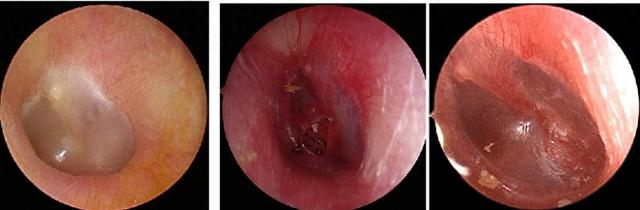

鼓膜有时会吹弹可破

鼓膜外伤性穿孔

引起鼓膜穿孔的几种原因